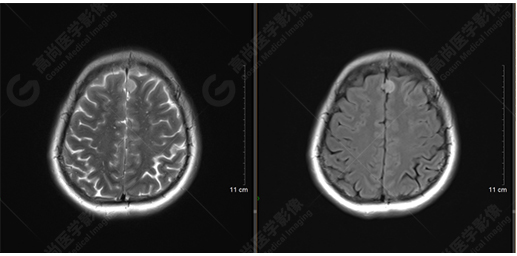

下面是其他神經(jīng)纖維束成像:

胼胝體束、雙側(cè)扣帶束及額枕束形態(tài)可,纖維束未見明顯破壞,未見明顯稀疏減少。大腦鐮旁的病灶對(duì)神經(jīng)纖維束走行并沒有什么影響。